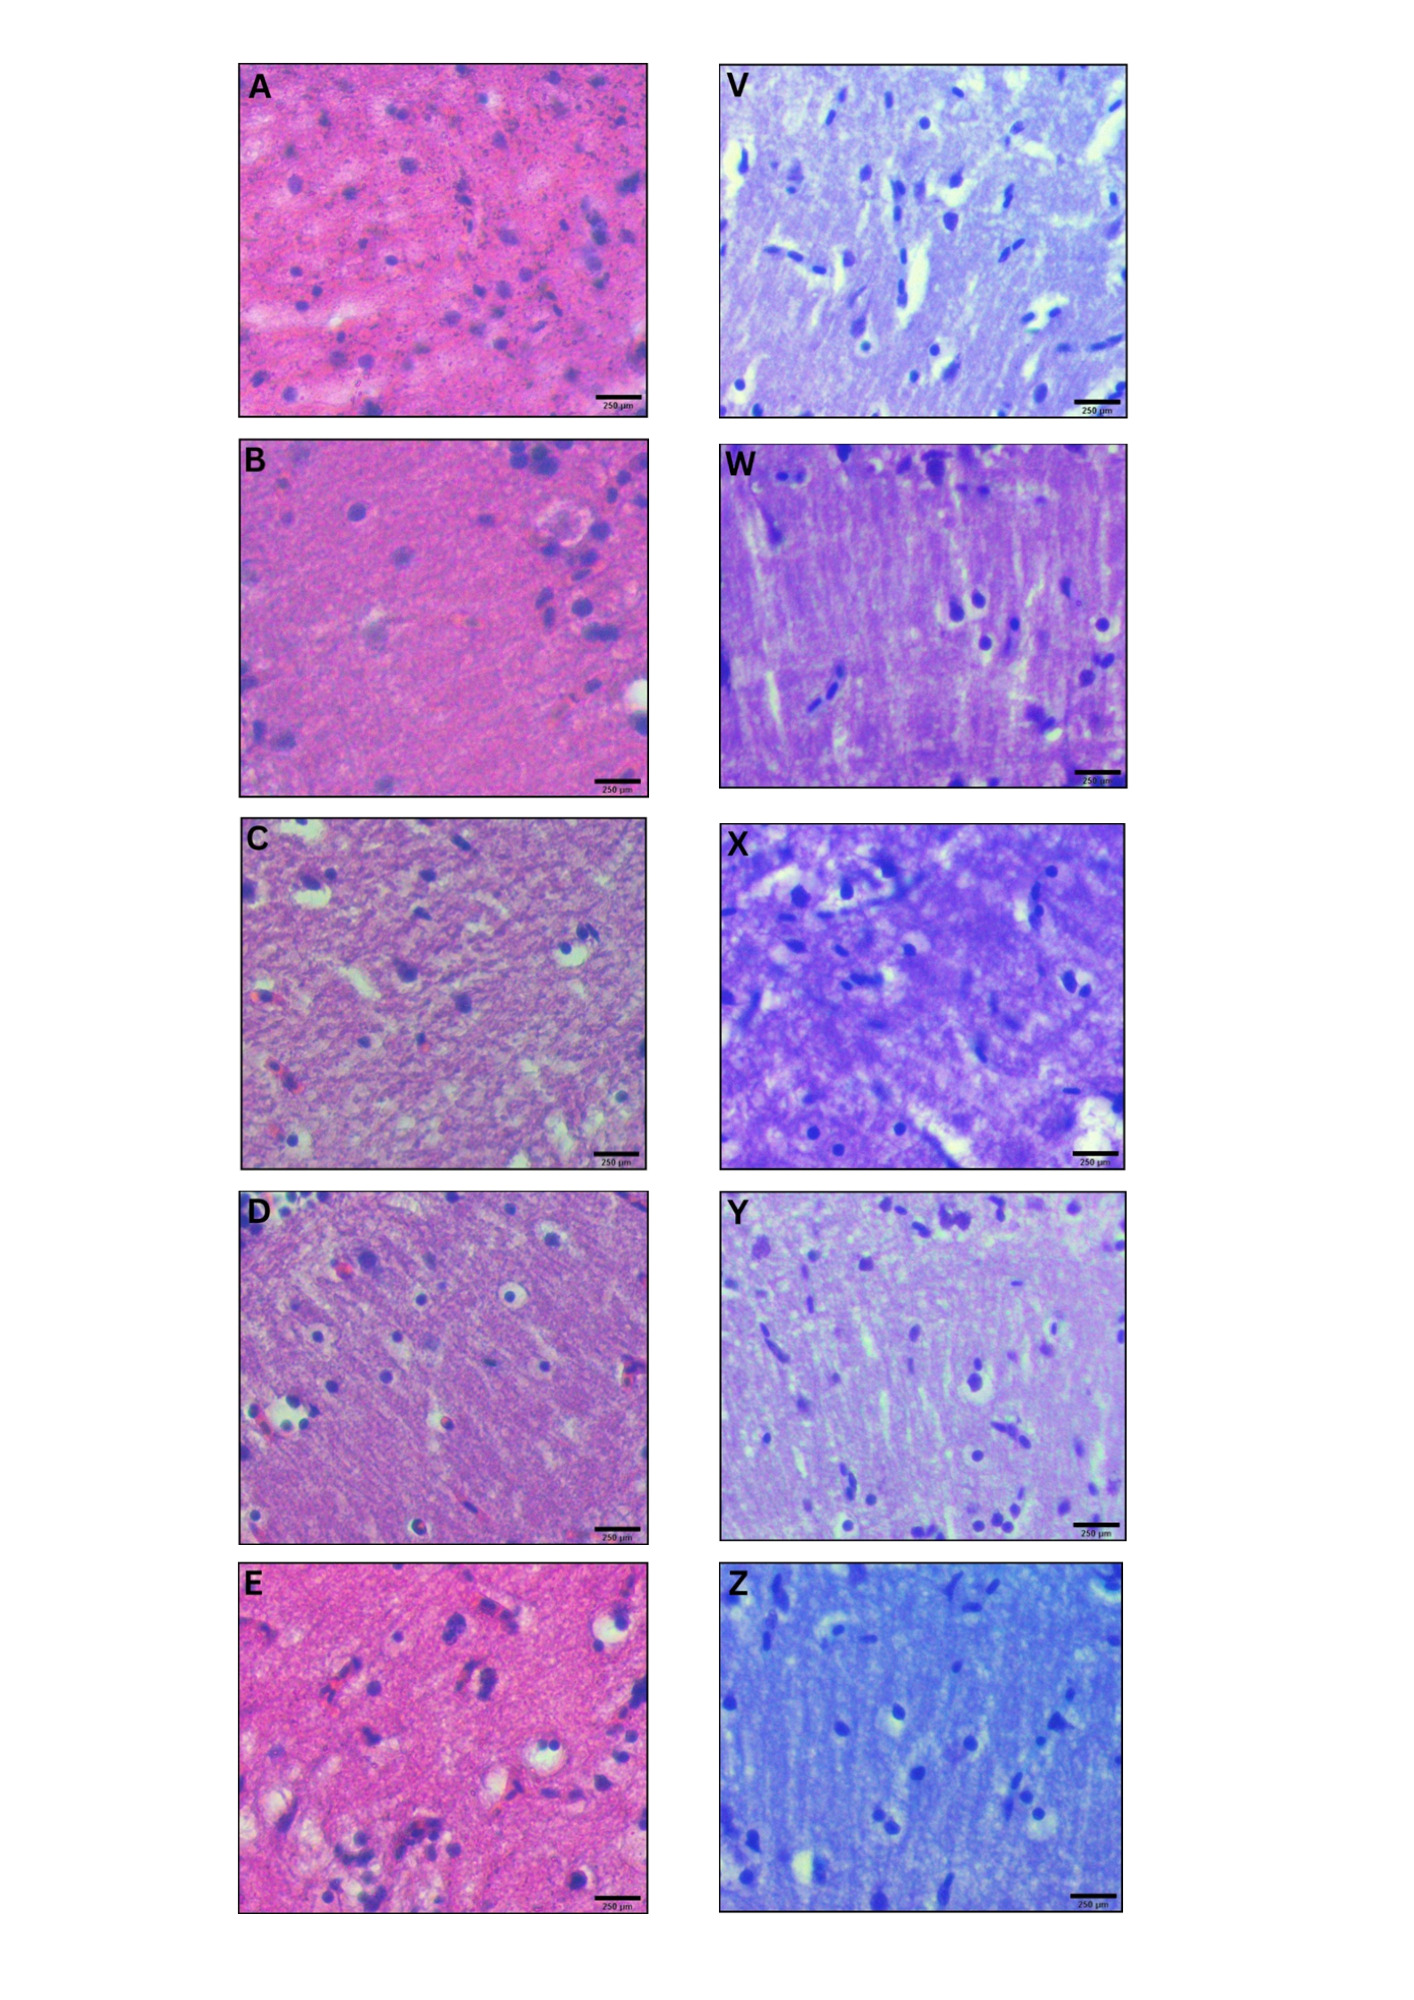

Parkinson’s disease (PD) is a neurological condition affecting the motor functions of the brain, characterised by the degeneration of dopaminergic neurons in the substantia nigra pars compacta region. The primary symptoms include dyskinesia, bradykinesia and resting tremors. This study investigated the potential impacts of Mitragyna speciosa or known as kratom on zebrafish with PD. 1-methyl-1,2,3,6-tetrahydropyridine (MPTP) solution was administered intraperitoneally to zebrafish to develop Parkinson’s symptoms in 2 to 3 days, followed by three concentrations treatment of kratom, for 28 days. On day 28, locomotor behaviour was evaluated to determine the duration spent in the top, middle, and bottom zones, total distance travelled and swimming speed. Then, the zebrafish were euthanised and preserved in a 10% formalin solution. Fixed zebrafish were processed and embedded in paraffin blocks for haematoxylin and eosin, and cresyl violet staining. The results of treatment groups showed that kratom had a neuroprotective impact, increasing time spent from bottom to top zone, distance travelled and swimming speed compared to the negative group. Moreover, the treatment groups experienced a rise in neuron regeneration and an enhancement in neuron appearance following a 28-day exposure to kratom. In conclusion, kratom shows promise as a potential treatment for PD by effectively reducing symptoms and improving movement.

Penyakit parkinson adalah keadaan saraf neurologi yang mempengaruhi fungsi motor otak yang dicirikan oleh degenerasi neuron dopaminergik pada bahagian substantia nigra pars compacta. Gejala utama penyakit ini termasuklah diskinesia, bradikinesia dan gegaran berehat. Kajian ini dijalankan untuk menyiasat potensi kesan kratom terhadap ikan zebra dengan penyakit parkinson yang dihasilkan. 1-methyl-1,2,3,6-tetrahydropyridine (MPTP) diberikan secara intraperitoneal kepada ikan zebra untuk mewujudkan gejala parkinson dalam tempoh 2 hingga 3 hari, diikuti dengan rawatan tiga kepekatan Mitragyna speciosa yang berbeza selama 28 hari. Pada hari ke-28, tingkah laku lokomotor dinilai untuk menentukan tempoh masa yang dihabiskan di tiga zon yang berbeza iaitu zon atas, tengah dan bawah, jumlah jarak perjalanan dan kelajuan berenang. Kemudian, ikan zebra dimatikan dan diawet dalam larutan formalin 10%. Seterusnya, ikan zebra diproses dan dibenamkan dalam blok parafin untuk pewarnaan hematoksilin & eosin dan Cresyl Violet. Keputusan kumpulan rawatan menunjukkan bahawa kratom mempunyai kesan neuroprotektif, meningkatkan masa yang dihabiskan dari zon bawah ke zon atas, jarak perjalanan dan kelajuan berenang berbanding kumpulan negatif. Selain itu, kumpulan rawatan mengalami peningkatan dalam penghasilan semula neuron dan peningkatan dalam penampilan neuron berikutan rawatan selama 28 hari menggunakan kratom. Kesimpulannya, kratom menunjukkan potensi besar sebagai rawatan alternatif untuk penyakit parkinson dengan mengurangkan gejala secara berkesan dan meningkatkan pergerakan lokomotor.